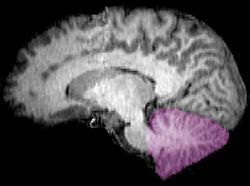

Cerebellum sag.jpg

الشكل 1b: صورة تصوير الرنين المغناطيسي تبين منظراً mid-sagittal للمخ البشري، ويبدو فيه المخيخ باللون البنفسجي